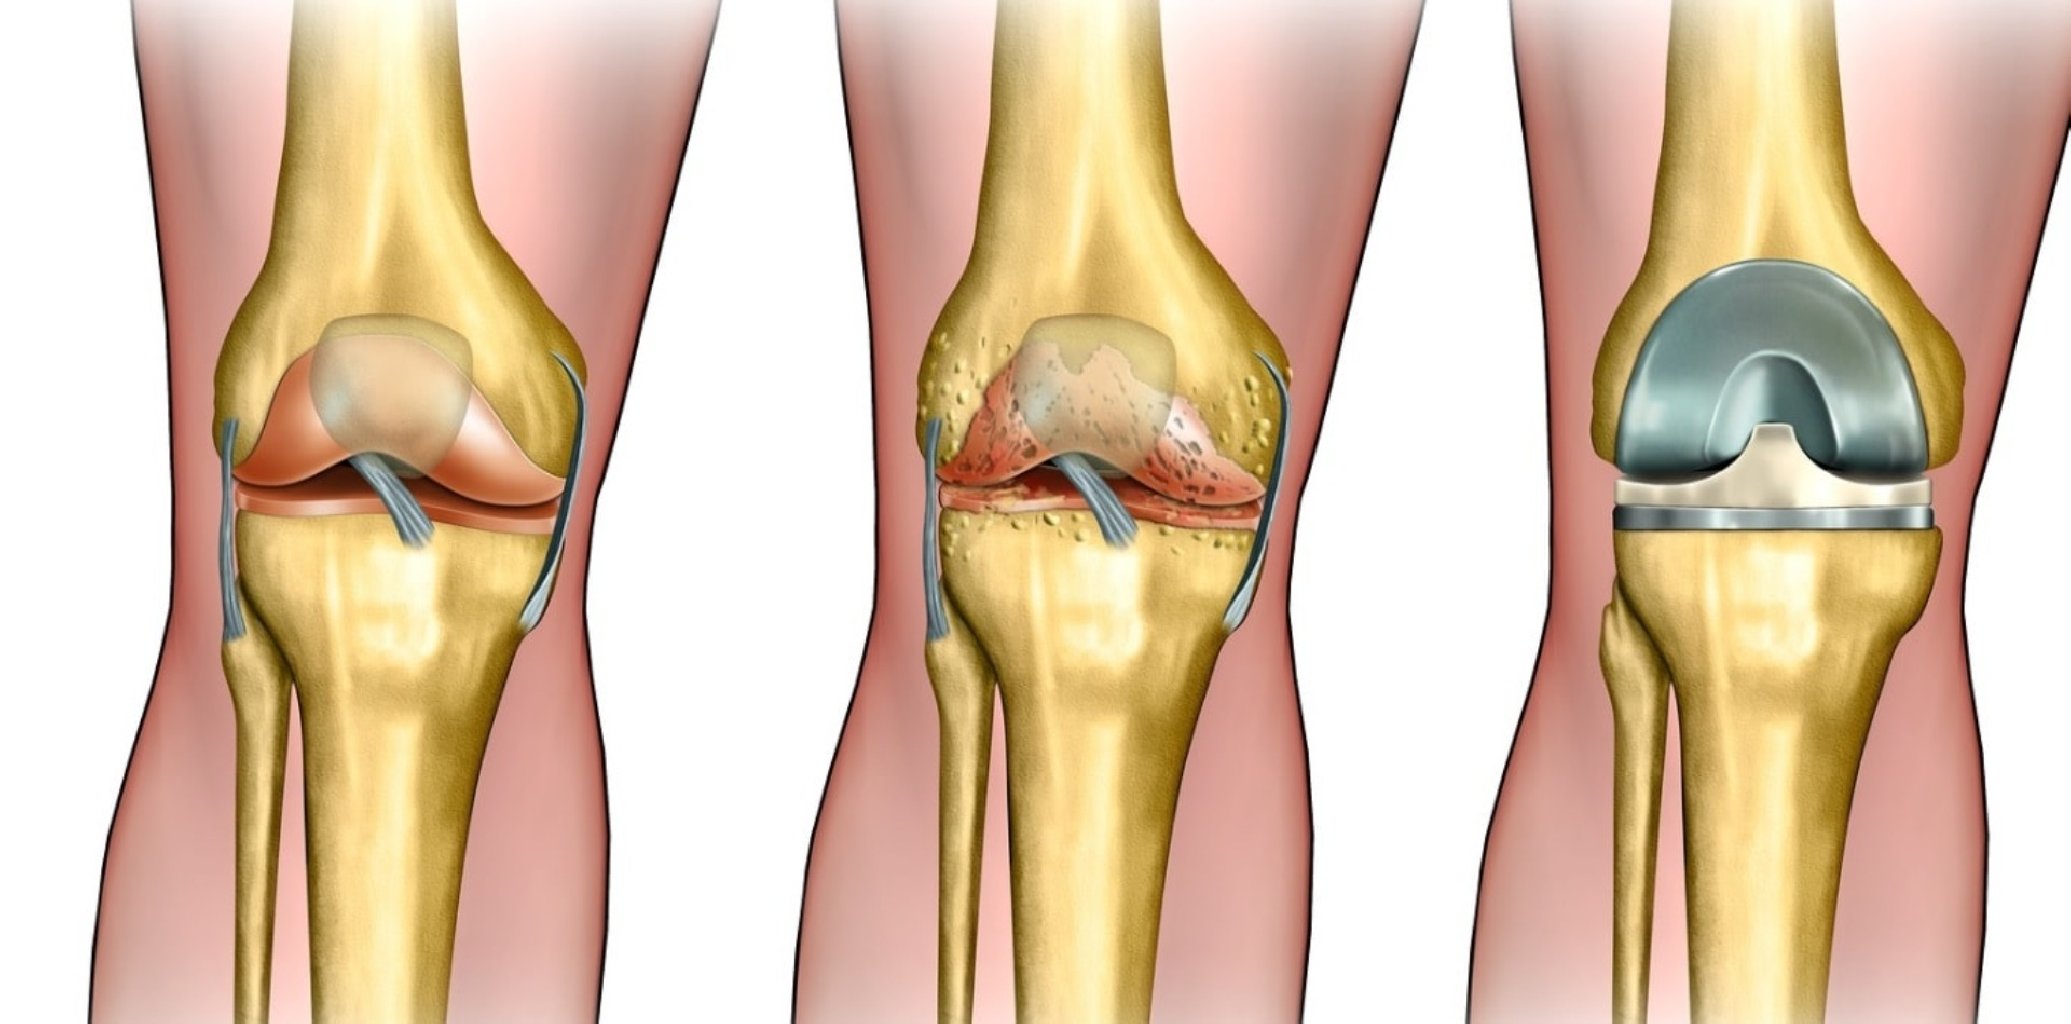

Osteoartrit: Ən çox görülən artropatiya növü olan osteoartrit, oynaq qığırdaqlarının tədricən aşınma ...

Artrozun müalicəsi simptomların aradan qaldırılmasına, birgə funksiyaların yaxşılaşdırılmasına və hə ...

Osteoartritin Səbəbləri Osteoartritin dəqiq səbəbi bilinməsə də, bir sıra risk amilləri tanınır: ...

Diz Kirəçləşməsinin Müalicəsi Yaşam Tərzi Dəyişiklikləri Kilo Vermək: Əlavə çəkinin azaldılmas ...